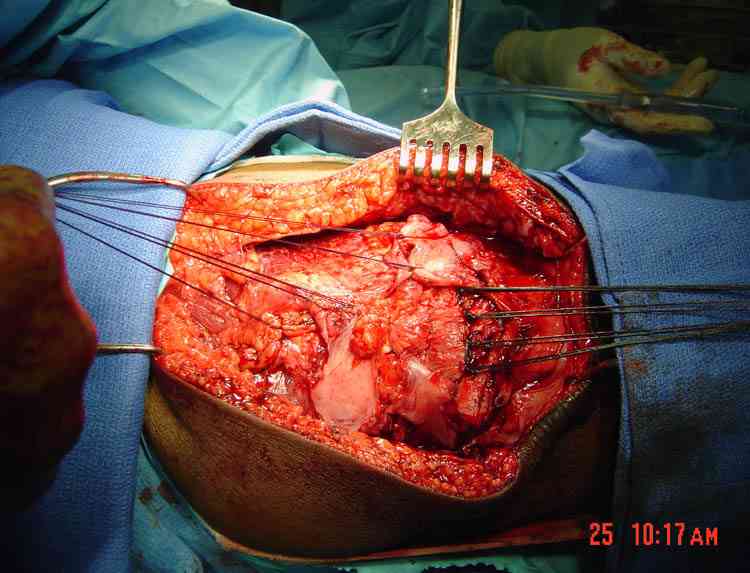

Только однажды пришлось применить технику низведения надколенника аппаратом Илизарова после двухстореннего застарелого (более 8 месяцев) повреждения связки надколенника. Через надколенник две паралельные спицы, низвели надколенник за короткое время и вторично провели пластику собственной связки надколенника.

Для восстановления данного перелома, перед началом

операции, под наркозом сделал бы редрессациию

коленного сустава. Уверен, что надколенник

опустится, но низведенный надколенник трудно удержать и добиться фиксации фрагментов из-за малых размеров.

Вместо фиксации перелома предпочтительно вести как

разрыв места прикрепления сухожилия в нижнем полюсе.

Такие повреждения фиксируются немного легче, чем

переломы надколенника.

Сначало надо освежить нижний полюс и удалить остаточные кости с образованием культи связки. Без удаления кости в дальнейшем будут болезненные проявления из-за несросшихся фрагментов.

Швы проведенные через параллельные туннели в

надколеннике, три или четыре N5 Ethibond, механически удержат до сращения.

Без необходимости сложной пластики, технику широко

применяем также для лечения разрывов quadrips связки.

Швы с двойной иглой в концах начинаем из дистальной части связки, подобие завязывания шнурков.

Проксимально выводим в середине связки, далее нити проводятся через предварительно сделанные паралельные туннели (2.5 мм сверлом), завязываются на верхнем участке надколенника в разгибании. Количество туннели зависит от количества швов, на одно больше, крайние одиночные, а серединные можно пропустить по две нитки сразу.

На снимке восстановление разрыва quad связки, только швы завязывается внизу надколенника, и примерный рисунок техники.

В приложении фото пациента с переломом надколенника 3 месячной давности. После мобилизации отломков, 4 главой мышцы бедра и полного разгибания голени оставался диастаз между костными фрагментами в 2 см. В связи с этим наложили модуль из аппарата Илизарова - 2 опоры и 2 спицы (в верхнем полюсе надколенника и верхней трети большеберцовой кости). Очень медленно (в течение 15 минут) путем накручивания гаек на стержнях растянули 4 главую мышцу бедра и устранили диастаз. Аппарат демонтировали и выполнили остеосинтез <стягивающей петлей>. Через 6 месяцев фиксаторы удалены. Автор данного <хирургического трюка> профессор из Австрии Vilmos Vecsei (<Гений ортопедии>, 2004, № 4, С. 94-95). Ваш случай не совсем идентичный по давности травмы и малой величине дистального отломка, но описанный <трюк> может оказаться полезным и при выполнении операции, которую рекомендует Джолдас.